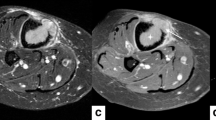

Figure 7 shows the results of one of the sonications of the in vivo experiment in a swine model. An area of elevated T2 values in the marrow, adjacent to the cortical bone in the US beam path appeared on the T2 maps acquired during heating (Fig. 7a). From the plot of the T2 values within an ROI over time (Fig. 7c), we observed that the highest T2 values appeared at the end of the sonication. We measured a T2 rise of 231 ms within the bone marrow, which corresponded to temperature change of 33 °C from baseline according to the data from the calibration experiment. The in vivo experiment showed excellent correspondence between the area of T2 elevation in marrow during the ablation and the resulting non-enhancing area in the post-contrast images (Fig. 7b).

T2 measurement in in vivo bone marrow: a T2 map during ablation of a single sonication, showing the ROI; b post-contrast 3D Fast SPGR image after ablation (total of six sonications per location); c plot of T2 values within the ROI over time; the highlighted area shows the approximate duration of the sonication